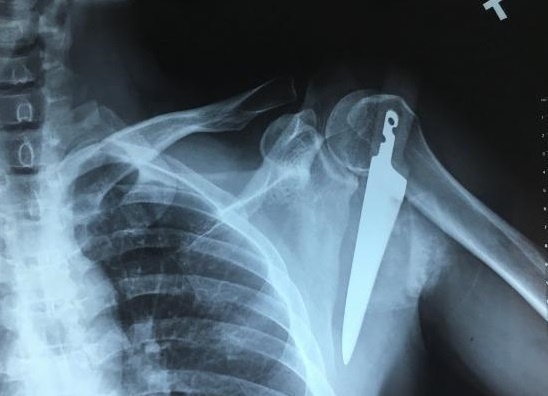

Bệnh nhân nhập viện trong tình trạng mệt, sốc do đau, tụt huyết áp, liệt hoàn toàn cánh tay phải. Theo các bác sĩ đây là loại chấn thương phức tạp hiếm gặp trên thế giới.

Khi đi vào bếp, người đàn ông vô tình vấp ngã và bị dao găm vào vai, phải nhập viện cấp cứu.